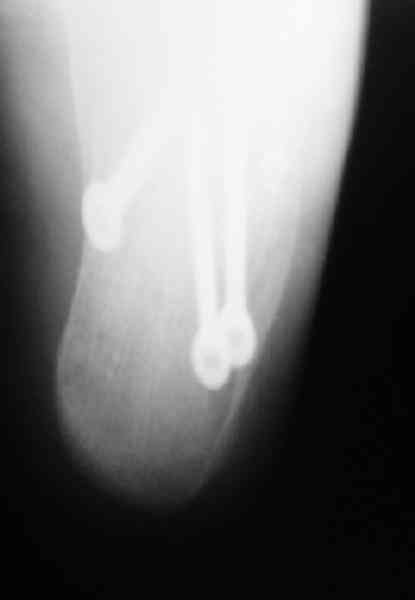

Если нет опыта в остеосинтезе пяточной пластиной то лучше начать с экскохлеации полости кистозного образования и заполнения его остеоиндукторами Коллапан, Тутопласт, etc.Закрытая репозиция с рентгенконтролем на столе и перкутанная фиксация спицами пяточного бугра с фиксацией в эквинусе могут дать вполне приемлемый результат.

Вправление задней фасеты с восстановлением таранно-пяточного угла возможно минимально-инвазивным методом Essex-Lopresti - под ЭОП или графическим контролем введенной в пяточный бугор толстой спицей или стрежнем Штеймана, которые служат рычагом. Для удержания вводим несколько тонких спиц Киршнера, фиксация в эквинусе.Подробнее в Margo anterior 1-2 2000\издание АО Матис в России, на сайте www.mathys.ru в архиве есть все выпуски. Метод внедрен у нас с 2000 года и дает неплохие результаты.

Уважаемый Антон Андрианов. В отделении сочетанной травмы U,24 г Екатеринбурга также используется подобная методика. Предварительно делаем КТ. Предоперационное планирование возможности управления отломками. Мы выполяем репозицию шилом. Фиксацию крупных отломков спицами, а затем репозицию и фиксацию более мелких фрагментов. Кстати, на сайтеАО Матис Margo anterior 1-2 2000 - нет (почему-то?). Было бы интересно узнать как и куда вы вводите спицы.

Действительно архив Margo Anterior начинается с 2001 года.Но я могу эту статью по лечению переломов пяточной кости,очень обстоятельную, санировать и выслать мылом на ваш адрес или разместить на rapidshare ru и указать ссылку на форуме. несколько тонких спиц вводятся в разных направляениях при многофрагментарных переломах иногда через подтаранный сустав для удержания репозиции. Их и стержень удалем через 6 недель.